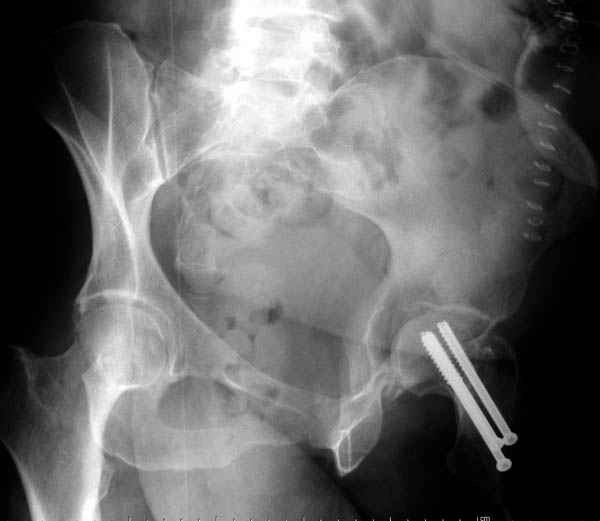

Уважаемые коллеги! С прошедшеми Вас праздниками. Теперь ближе к трудовым будням. Поступила 16 летняя девушка неделю назад. Механизм травмы падение с 5 этажа. Краткий диагноз:закрытый перелом левой ключицы, левого плеча, закрытый вертикально и ротационно нестабильный перелом костей таза:закрытый перелом левой подвздошной кости, переломы лонной кости справа, перелом обоих колонн вертлужной впадины слева;субкапитальный перелом шейки левой бедренной кости со смещением. По тактике лечения таза возникли следующие вопросы: 1. С чего начать - фиксации переломов вертлужной впадины или устранения деформаций таза? 2. Надо ли фиксировать шейку или фиксировать бедро в аппарате вместе с тазом, а после сращения таза планировать ТЭП ТБС? Если имеются еще какие подводные камни, будем рады выслушать.Спасибо.

Долгое ожидание повышает риск АВН головки,

рекомендуется ургентная фиксация шейки в первые сутки, а в дальнейшем таз.

В данный момент скелетное вытяжение поучается через перелом шейки, а фиксированный перелом шейки будет участвовать в процессе вытяжения через каннюлированные шурупы.